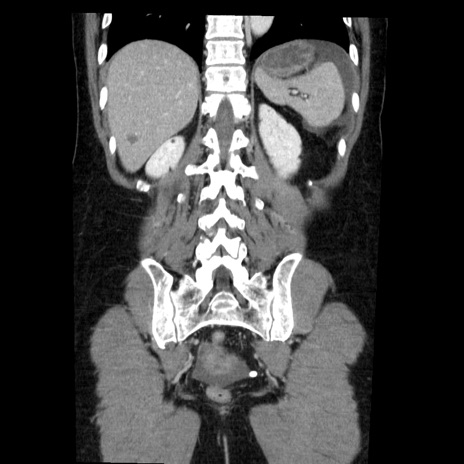

症例6(冠状断像)

【症例】50歳代女性

【主訴】下腹部痛

【現病歴】本日朝より下痢2回あり。 昼食を食べた後、嘔吐3回、下腹部痛認め、症状軽快せず、当院救急搬送。

最終食事:本日昼(生ものなし)。 昨日の夜、刺身を食ぺたとのこと。周囲に同様の症状の者なし。普段、排便は毎日あるとのこと。

【既往歴】卵巣癌術後(8年前に当院で卵巣摘出)

【身体所見】 意識清明、腹部:平坦、腸蠕動音→、やや硬、下腹部自発痛・圧痛あり、反跳痛あり、筋性防御なし。

【データ】WBC 16000、CRP 0.01